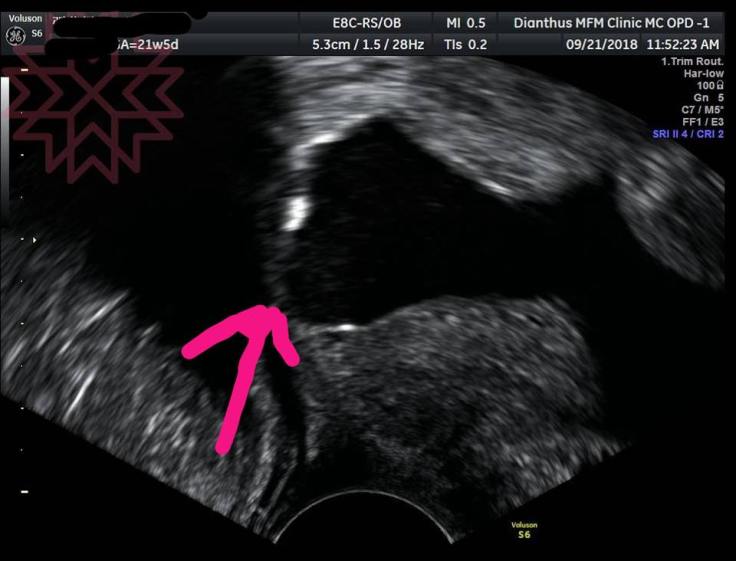

第一張照片箭頭所指

是手術前羊水袋膨出的地方

已經完全看不到子宮頸結構